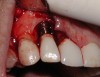

With all of the success seen in the dental community relative to implant placement, dentists are now seeing a more pronounced trend in dental implant care: an increase in the bacteriologic and/or traumatogenic occlusion-mediated loss of tissue integrity, accompanied many times by alveolar bone loss. The most common terminology applied to this condition is peri-implantitis (Figure 1). As replete as the dental literature is with success story after success story, there is virtually no detailed and specific prospective clinical trial data on the diagnosis and management of the peri-implant diseases, which result in soft tissue inflammation and the potential for alveolar bone destruction that may lead to the loss of the implant.

Fig 1. This implant was placed in March 2006. Peri-implantitis was clinically evident in April 2008, with bleeding on probing, suppuration, and increasing probing depth.

Figure 1